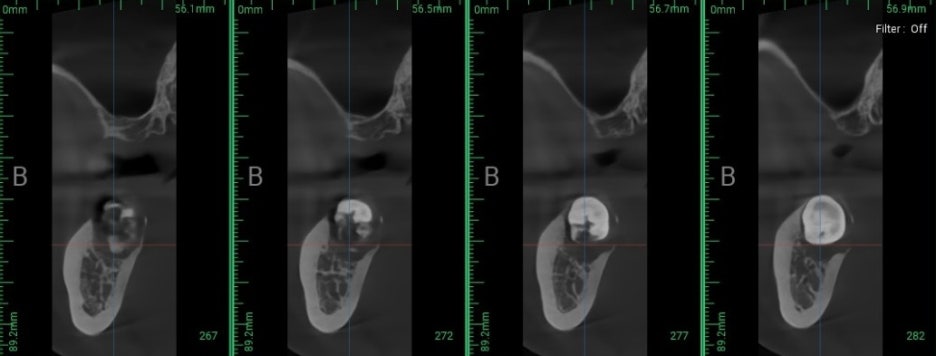

민락 치과 에서 보여드리는

술후 엑스레이를 확인해 보면

잇몸 치료를 병행했기 때문에

전반적으로 치석도 제거되었으며,

임플란트 역시 잘 식립되어 있습니다.